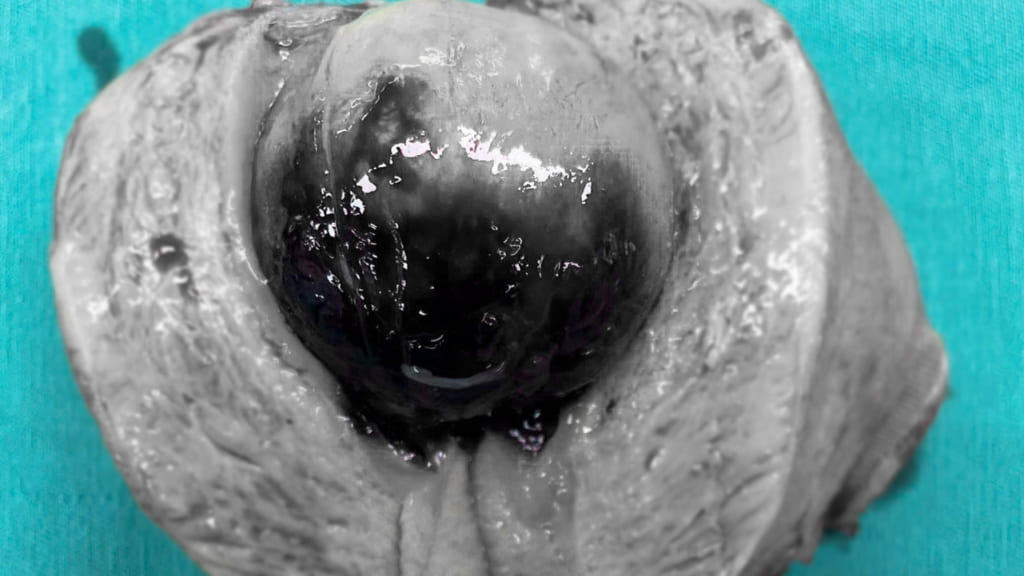

Bệnh nhân nhập viện trong tình trạng mệt mỏi, hoa mắt, chóng mặt, da xanh xao, kết quả xét nghiệm cho thấy thiếu máu nặng do rong kinh, cường kinh kéo dài. Qua thăm khám và siêu âm, các bác sĩ phát hiện khối polyp buồng tử cung lớn chiếm gần toàn bộ lòng tử cung, là nguyên nhân chính gây mất máu nghiêm trọng.

Trước diễn biến nguy hiểm, ekip bác sĩ đã nhanh chóng hội chẩn và chỉ định phẫu thuật cắt polyp buồng tử cung. Trước mổ, bệnh nhân được truyền 3 đơn vị khối hồng cầu. Nhờ kinh nghiệm chuyên môn vững vàng cùng hệ thống trang thiết bị hiện đại, ca phẫu thuật diễn ra an toàn, loại bỏ hoàn toàn khối polyp, kiểm soát tốt tình trạng xuất huyết. Sau mổ, bệnh nhân hồi phục ổn định và được xuất viện an toàn.